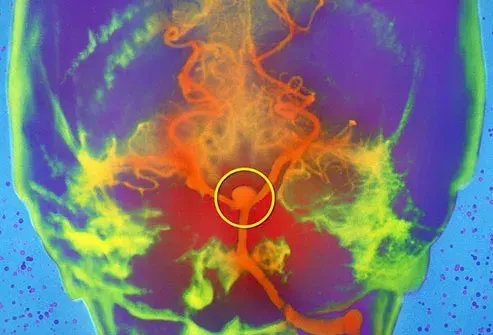

Anévrisme cérébral

Un anévrisme cérébral est un point faible dans un vaisseau sanguin. Il y a généralement des ballons ou des renflements et se remplit de sang. Beaucoup ressemblent à une baie suspendue sur une tige mince. Ils se forment souvent sur les artères à la base du cerveau. Certains anévrismes fuient ou se ruptent. Cela provoque des saignements dans le cerveau ou dans la zone entre votre cerveau et sa doublure. Ce sont des traits hémorragiques. Ils peuvent commencer comme des maux de tête mais peuvent entraîner des crises de nausées et la mort.